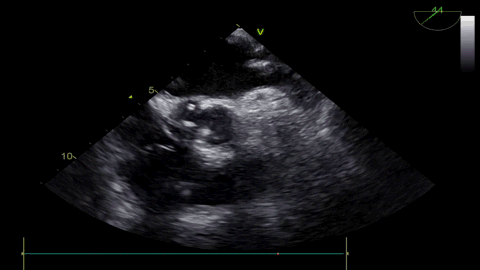

VenusA26号完全释放

最后一枪造影

超声显示人工瓣膜工作良好,微量瓣周漏,术后一周顺利出院,术后随访无并发症,恢复良好。